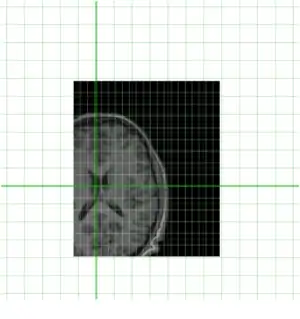

Clearly they are not aligned or "registered" to each other so we have to use a tool such as minctracc or mritoself in order to align them as such:

To do this we can use a command such as this:

minctracc -lsq9 indiv.mnc model.mnc align.xfm

The -lsq9 argument here is instructing minctracc to recover 3 rotations, 3 translations and 3 scales. Note that the output of this step is not an aligned image but an output (linear) transform file which contains a 4x4 tranformation matrix. This consists of a 3x3 affine transformation plus 3 translations should they be needed. An example of one of these files is below: